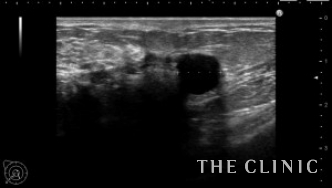

エコー所見です。石灰化の強いしこりです。

今回は大きな石灰化したしこりの摘出をしましたが、周囲に硬いしこりが残ったため確認すると瘢痕化したしこりでした。

再度エコーを確認すると瘢痕組織の周囲に小さなオイルシストもあり、おそらく石灰化したしこりの一部が漏れ出し、強い炎症を伴い瘢痕化したと推測されます。